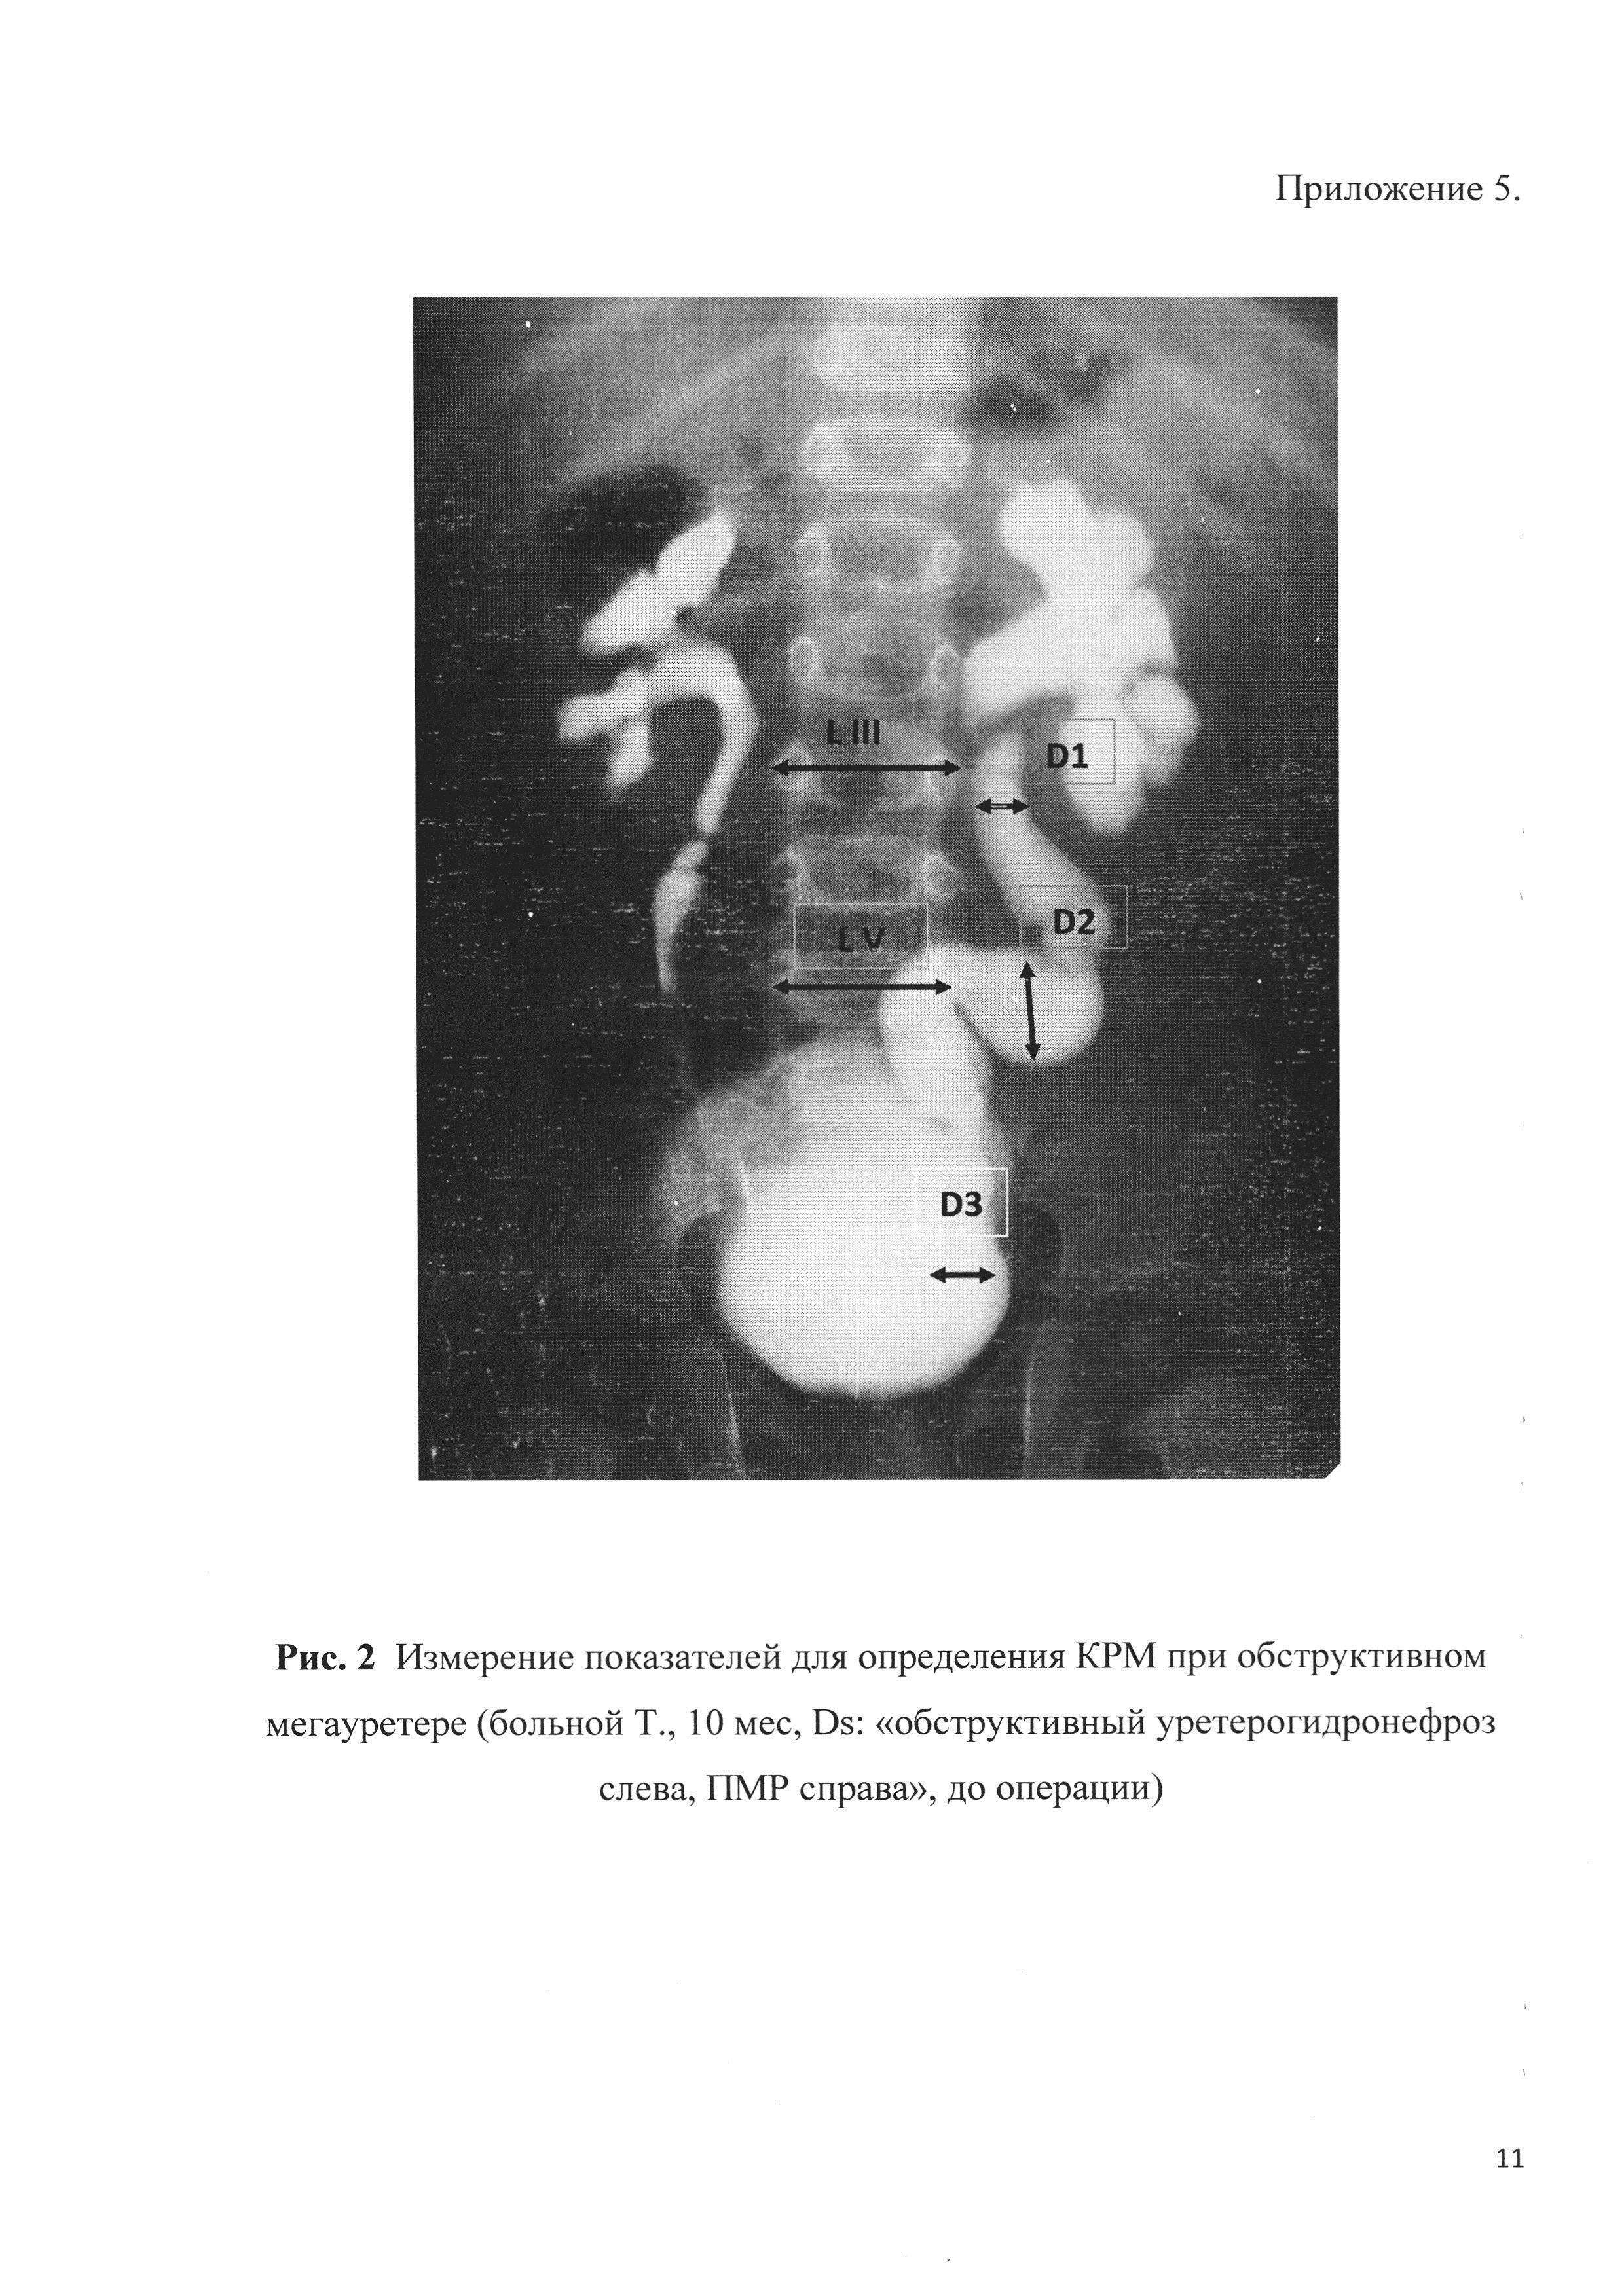

Рефлюксирующий мегауретер: Визуализация и медицинские изображения